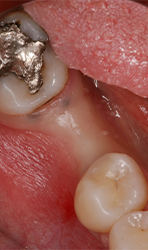

The Magnetic Max (Figs. 1-2) is useful for conservative root extraction.

Fig. 1

Maximum preservation of the alveolar housing and related gingival structures may be achieved following assisted atraumatic tooth extraction by an electrical mallet (Fig. 3).